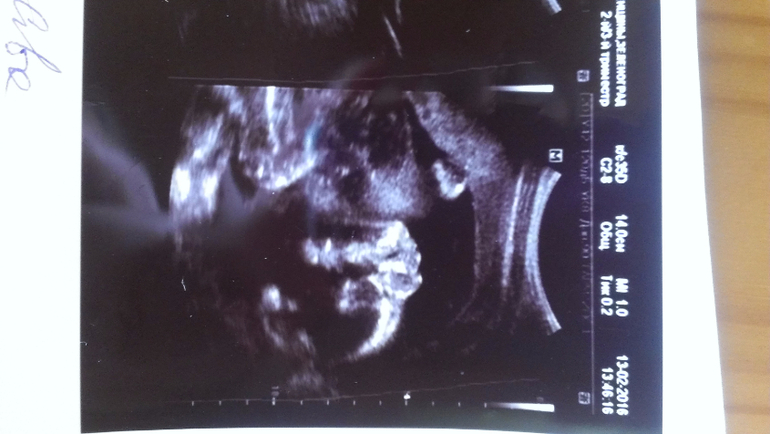

Внутриутробное развитие двойни/тройниНа узи в 20 недель уверенно сказали - два мальчика и на снимках так четко выделили, а неделю назад в другом центре врач как раз не очень уверенно, но предположила, что обе девочки...

На узи в 20 недель:

А у вас ну очень похожи на пацанов)

Вот мне тоже кажется, что, по крайней мере, с одним не могли ошибиться)) В любом случае, розовое (как и голубое) закупать не планировала, но люблю быть готовой.

Еще, все кто видел верхнее фото - сразу сказали, нос папин. Надеюсь, мальчику достался))